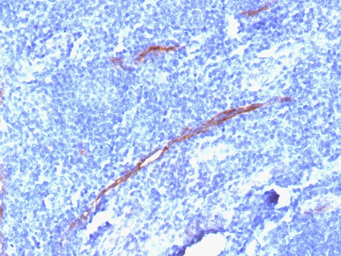

IHC-P analysis of human tonsil tissue using GTX34502 CD34 antibody [HPCA1/1806R].

CD34 antibody [HPCA1/1806R]

CD34 抗体 [HPCA1/1806R]